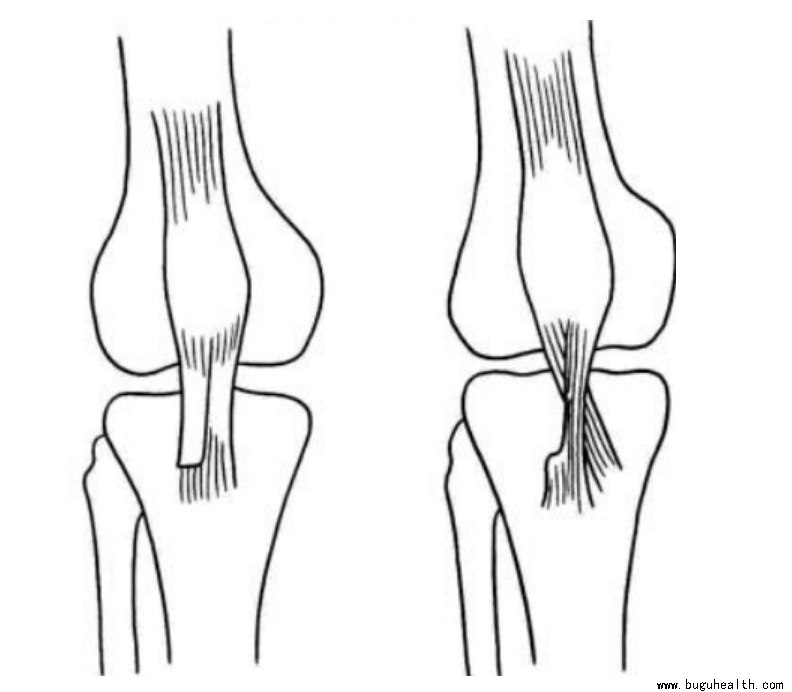

半腱肌腱转移术: